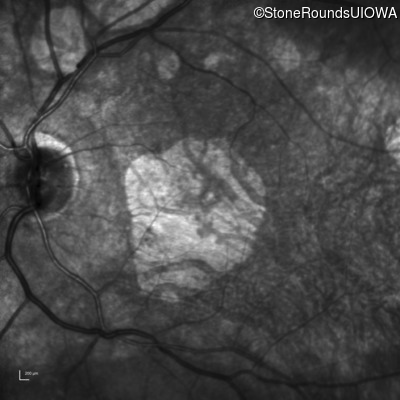

Optical Coherence Tomography - Right - 20/100

Exemplar / OCT Stack

Infrared Fundus Photograph - Right - 20/100

Exemplar